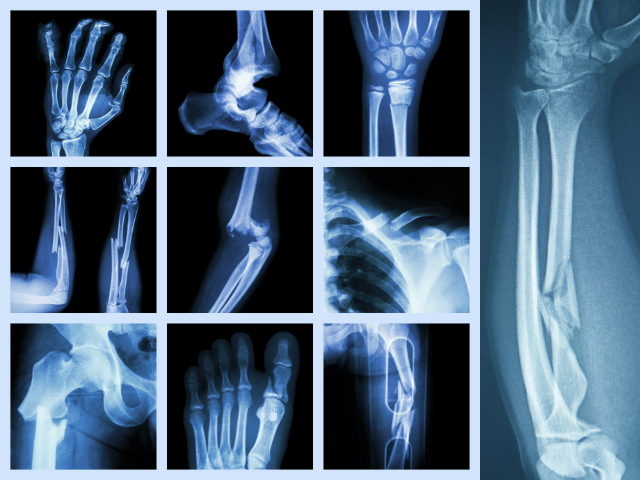

骨折の種類

骨折には、完全骨折、不完全骨折、開放骨折、閉鎖骨折などがあります。完全骨折は、骨が完全に折れている状態を指し、不完全骨折は、骨が一部折れている状態を指します。開放骨折は、骨が皮膚から突き出している状態を指し、閉鎖骨折は、皮膚が骨折部位を覆っている状態を指します。

加えて、骨折には、脊椎骨折、手首骨折、肘骨折、指骨折、肋骨折、脚の骨折、腕の骨折など、部位によって分類される場合があります。骨折の種類によっては、手術が必要な場合があります。